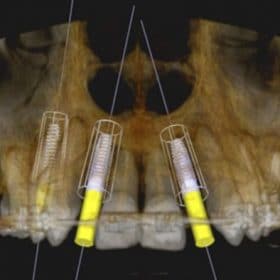

The following case illustrates 5 important components of placement and restoration of two-piece Zeramex XT implants:

Step 1: Pre-surgical 3D planning.

Step 2: Pre-prosthetic 3D planning.